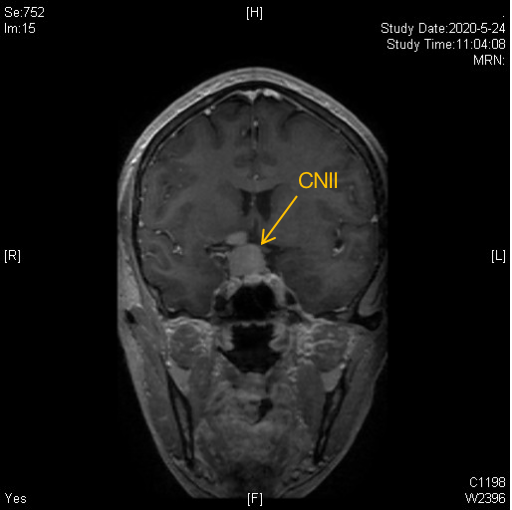

核磁共振所见:

鞍区可见哑铃形异常信号,大小约2.2*3.0*2.6cm,边缘清晰,增强后明显均匀强化,局部紧贴双侧海绵窦,蝶鞍扩大,鞍底稍下陷,视交叉受压上移。